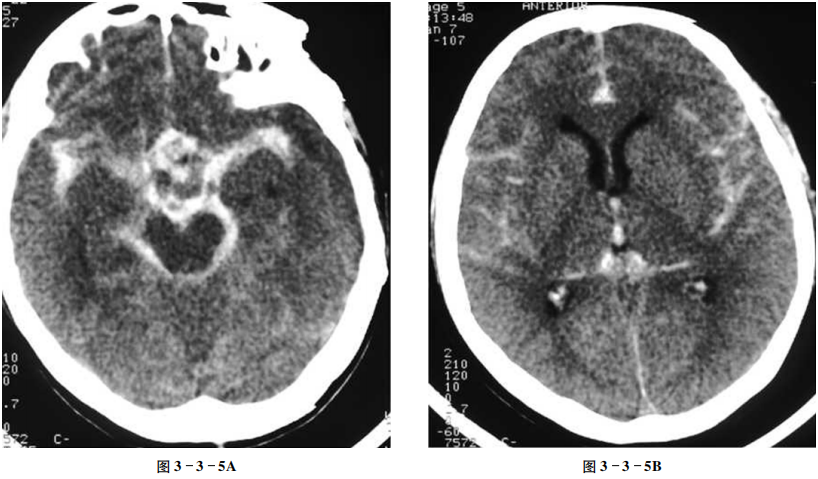

蛛网膜下腔出血

男性,65岁。突发头痛1天。

【CT征象】

平扫示鞍上池、环池、侧裂池及脑沟内铸型高密度影(图3-3-5A、B)。

【重要征象】

脑沟、脑池内铸型高密度。

【最终诊断】

蛛网膜下腔出血。